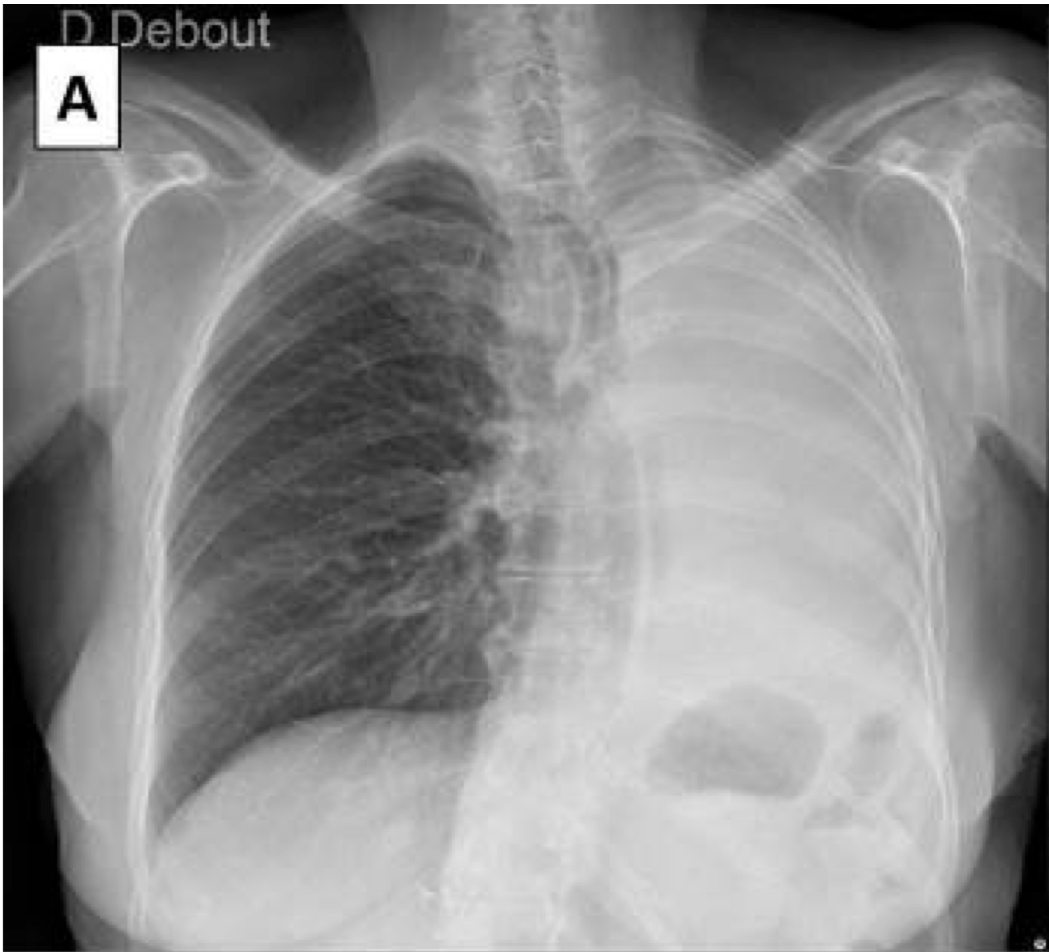

Selon cette image, quel est le diagnostic le plus probable

Alectasie, et ouais les diagnostics différentiels peuvent exister, on le voit car la déviation médiastinale est du côté de l'opacité

Etiologie ?

Indice : cette personne a de la fièvre

La fièvre oriente plutot pour une cause tuberculeuse